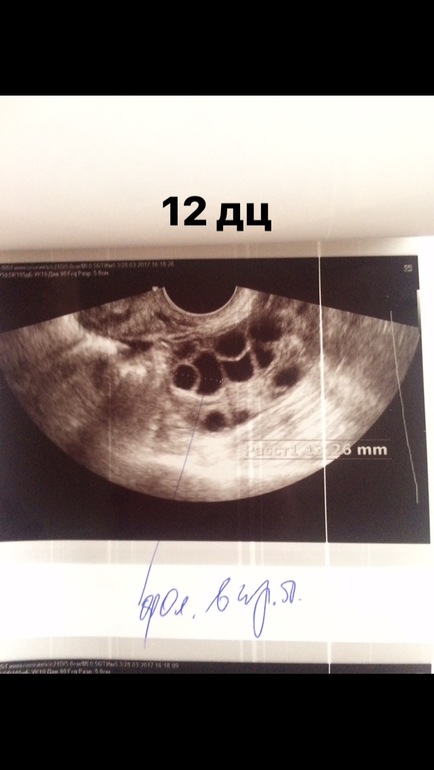

ФолликулометрияТолько приехала с фолликулометрии, и я в шоке! Смотрит она меня и говорит: - а вы знаете что у вас киста???

Я: 😧 как? Я неделю назад была у другого узиста и не было!

Короче девочки я расстроена не могу! В 2013 удаляли дермоидную кисту, и вот она снова?! Или врач могла ошибиться?! Не хочу опять на операцию, опять столько времени, сил, нервов и денег! Да и посмотрите, пожалуйста УЗИ , я пока а этом не сильна) вроде эндик маловат?